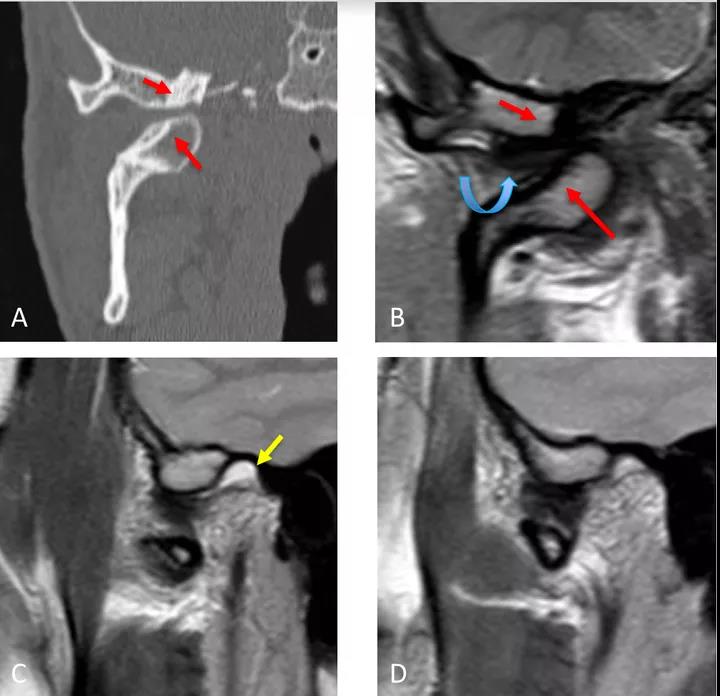

病例二:顳下頜關節脫位

冠狀面CT圖(A)和冠狀面PDWI圖(閉口)(B):顯示由于先前骨折導致的下頜髁突內側移位的顳下頜關節脫位,與骨折畸形愈合、前上髁和后顳嵴硬化(紅色箭頭)相關。關節盤位于下頜骨髁突和顳突之間,失去正常的形態(彎曲箭頭)。

矢狀位T2WI圖(閉口)(C):顯示正常位置的下頜骨髁突及關節積液(黃色箭頭)。

矢狀位PDWI圖(開口)(D)顯示髁突明顯偏移。